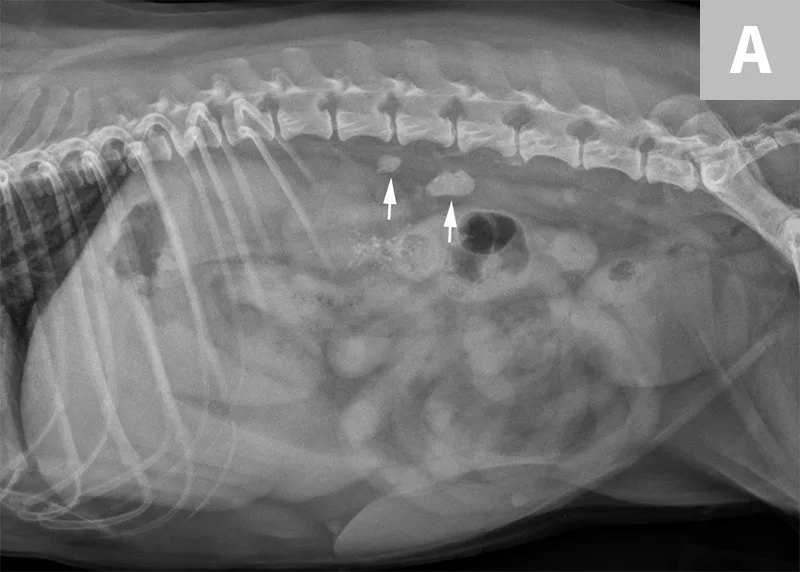

FIGURE 2A

A right lateral radiograph of a normal dog. Notice several circular soft tissue opacities superimposed over the retroperitoneal space. These represent end-on vessels with renal veins seen cranially (arrow) and deep circumflex iliac vessels seen caudally (arrowheads).